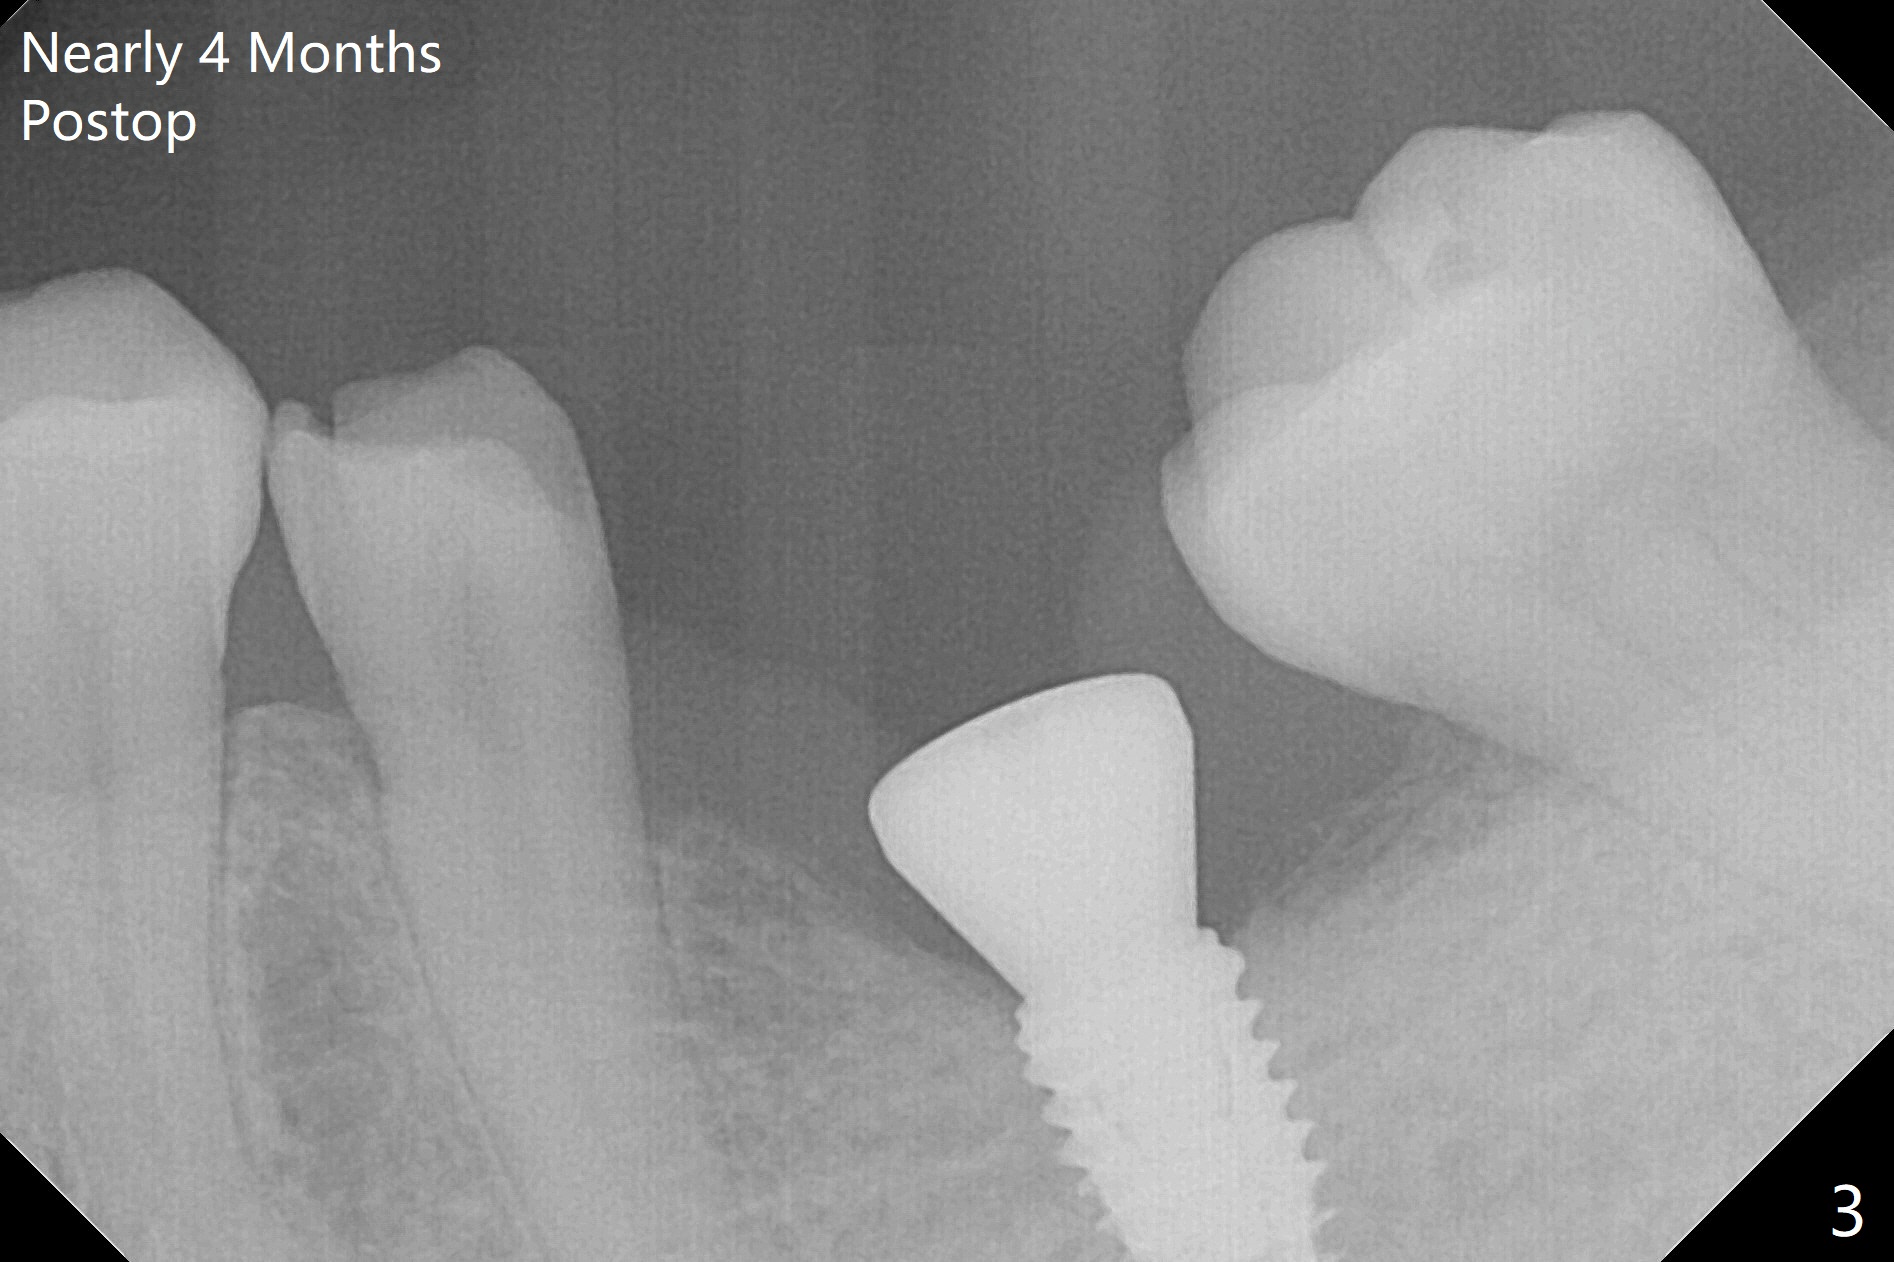

With 34 mg of Lidocaine and 17 mcg of Epinephrine (local infiltration), a 4.5x8.5 mm implant is placed with guide. The insertion torque is ~50 Ncm. It is placed in precise depth and in a short period of time (tolerable to the operators and patient, easier than mini-implant placement, Fig.1). There is no postop pain or paresthesia. The mesidistal position is within treatment plan (Fig.2). Miniimplants are placed to intrude #14 14 days prior. The teeth #16,17 and 32 are extracted 3 months postop. Minimal bone resorption at the crest is noted nearly 4 months postop (Fig.3). Bands and brackets are placed #18 upright 4 months postop (Fig.4 (14 niti wire)). The buccal and lingual view of the preop model shows that the supraerupted 1st molar (#14) has close relationship with the distal surface of the tooth #20 (Fig.5,6), accounting for the severe wear of the latter (Fig.8-11). The implant not only acts as an anchor to upright #18 in 4.5 months post banding (Fig.7 *), but also as an occlusal stop so that #18 has no interference to be moved. The stress on the implant results in radiating trabecular pattern (Fig.7,11 (9,11 months postop), as compared to before loading (Fig.1,3)). Restoring the distal contour of #20 with composite (Fig.12 C) makes it easy to close the space by adding porcelain the mesial surface of the implant crown. The crown/abutment is loose in China 7 months post cementation.